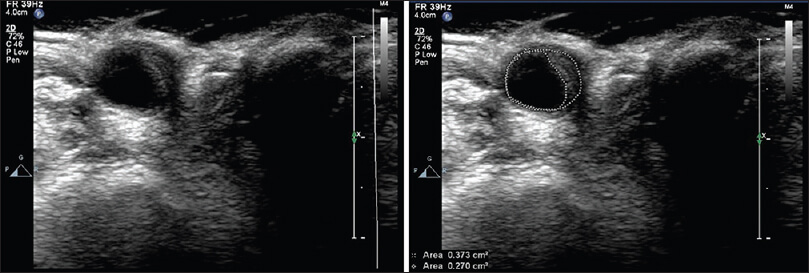

For reasons not entirely clear to me, I build up gunk on the walls of my blood vessels. My coronary arteries have needed cleaning and repair, and I’ve just been told that my right carotid artery is building up gunk and needs additional examination.